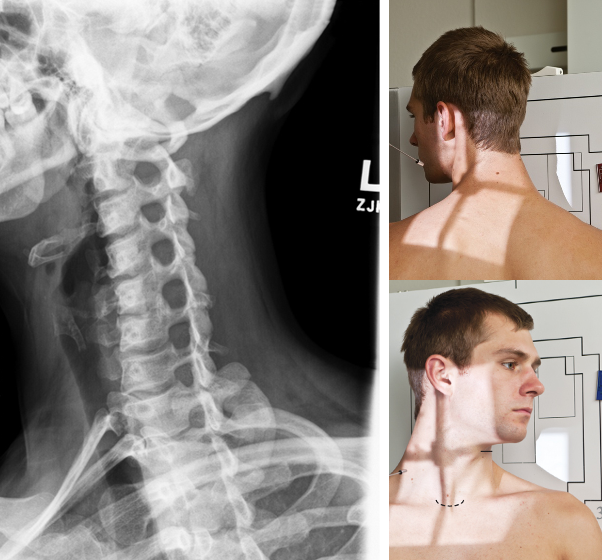

Lateral C-Spine

- IR 10x12 portrait, 72 SID **Upright bucky** - Position patient in lateral either sitting or standing with left shoulder against IR/bucky. Align MCP to CR and midline of IR- placing top of IR about 1-2” above EAM (top of ear attachment). Have patient relax and depress shoulders. Elevate chin so AML is parallel to floor. **Suspend on full expiration** - CR perpendicular to center of IR, entering C4 (upper level of thyroid cartilage). Collimate to 4 sides of anatomy (ST margins)